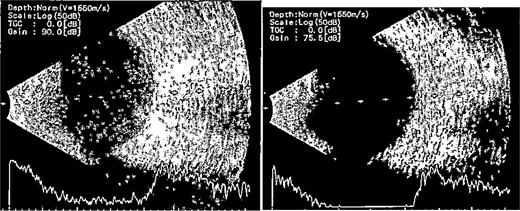

Patient 1: A 66-year-old Sudanese male presented to the emergency room with severe pain in his right eye 2 days post-phacoemulsification. Examination revealed only light perception, elevated intraocular pressure (IOP), a hazy cornea, hypopyon, and extensive pupillary membrane (Fig. 1). A B-scan ultrasound (Fig. 2). He underwent a vitreous tap and received intravitreal antibiotics.

B-scan ultrasound demonstrating mild to moderate vitritis in endophthalmitis case in patient 1.